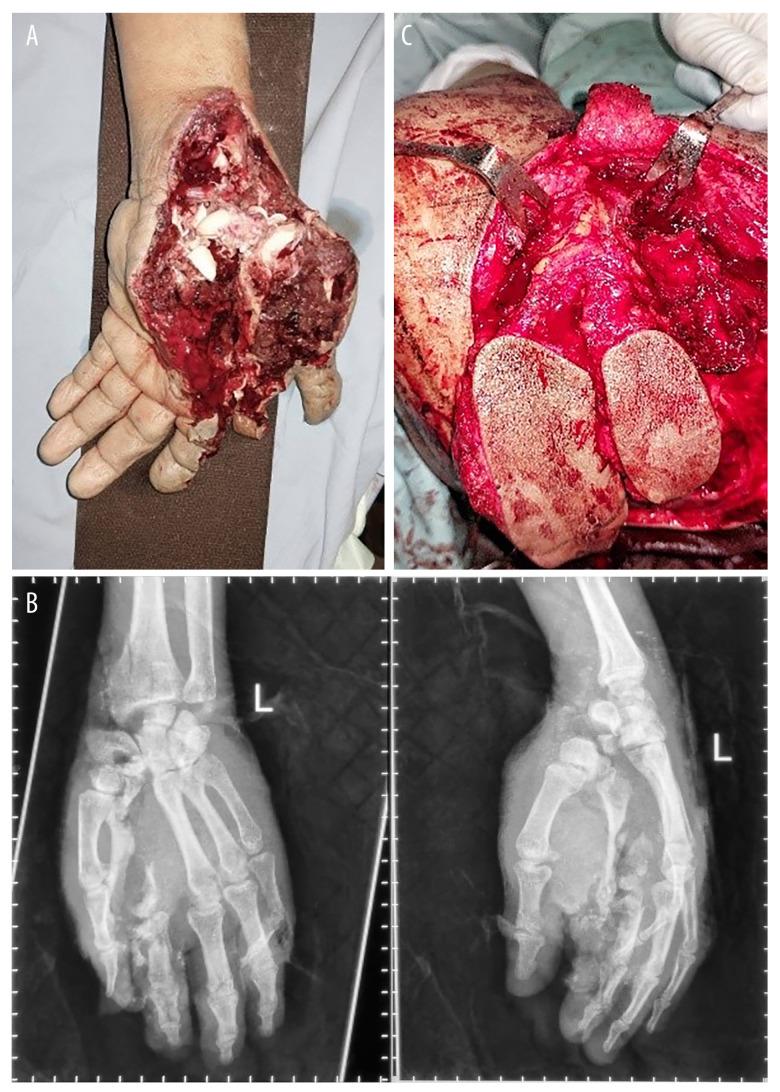

BACKGROUND The thumb is crucial for the aesthetic and functional aspects of the upper extremity. A crushed thumb injury can be particularly challenging, especially for individuals with high demands. Currently, there is no consensus on the best approach for treating a crushed thumb. The scapular flap, vascularized by the subscapular artery system, shows great potential as a free flap option. This report aims to highlight the use of a triple flap procedure to preserve the function of the crushed thumb. CASE REPORT A 47-year-old man had a severe injury to his left hand, resulting in significant soft tissue damage in the thenar region, an amputated thumb, and multiple fractures in the phalanx and metacarpal bones. The case was managed using a combination of scapular, parascapular, and osteo-cutaneous parascapular flaps. The first surgery focused on debridement and preserving viable structures, while the second surgery, performed 3 days later, involved the creation of a triple flap, utilizing the circumflex scapular artery and thoracodorsal artery as skin paddles. The flap remained viable, and 6 months postoperatively, the patient regained significant strength and functionality in his left hand. CONCLUSIONS This case demonstrates that severe hand injuries with thumb amputation require a strategic approach based on wound condition and reconstruction feasibility. Triple flaps can be an effective option for such injuries. This report highlights the challenges of treating severe hand crush injuries and emphasizes the importance of personalized surgical approaches for optimal outcomes.

背景 拇指对于上肢的美学和功能方面至关重要。拇指挤压伤可能特别具有挑战性,尤其是对于有高要求的个体。目前,对于治疗拇指挤压伤的最佳方法尚无共识。由肩胛下动脉系统供血的肩胛皮瓣作为游离皮瓣选择显示出巨大潜力。本报告旨在强调使用三联皮瓣手术来保留挤压伤拇指的功能。病例报告 一名47岁男性左手严重受伤,导致鱼际区域严重软组织损伤、拇指离断以及指骨和掌骨多处骨折。该病例采用肩胛皮瓣、肩胛旁皮瓣和骨皮肩胛旁皮瓣联合治疗。第一次手术重点是清创和保留 viable 结构,而3天后进行的第二次手术包括利用旋肩胛动脉和胸背动脉作为皮瓣形成三联皮瓣。皮瓣存活,术后6个月,患者左手恢复了显著的力量和功能。结论 本病例表明,伴有拇指离断的严重手部损伤需要根据伤口情况和重建可行性采取策略性方法。三联皮瓣对于此类损伤可能是一种有效的选择。本报告突出了治疗严重手部挤压伤的挑战,并强调了个性化手术方法对于实现最佳结果的重要性。